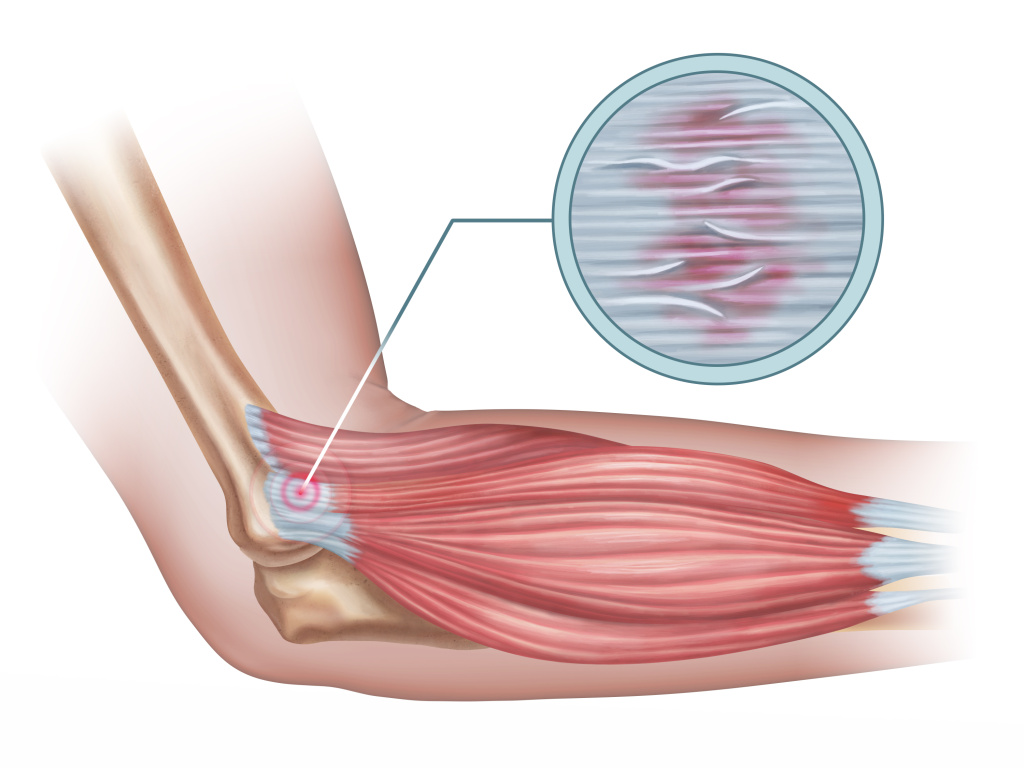

L’épicondylite est une pathologie affectant un ou plusieurs des tendons reliant les muscles extenseurs du poignet à l’épicondyle latéral du coude. L’épicondyle latéral du coude est un petit relief osseux de l’humérus (os du bras), situé au-dessus de l’articulation du coude et à la face externe du bras.

Le(s) tendon(s) atteint(s) présente(nt) de la douleur en raison d’un changement (volume, intensité, technique), d’une charge inadéquate imposée, d’un mouvement répétitif ou encore en raison d’une mauvaise posture/ergonomie. La douleur peut parfois progresser au niveau de l’avant-bras.